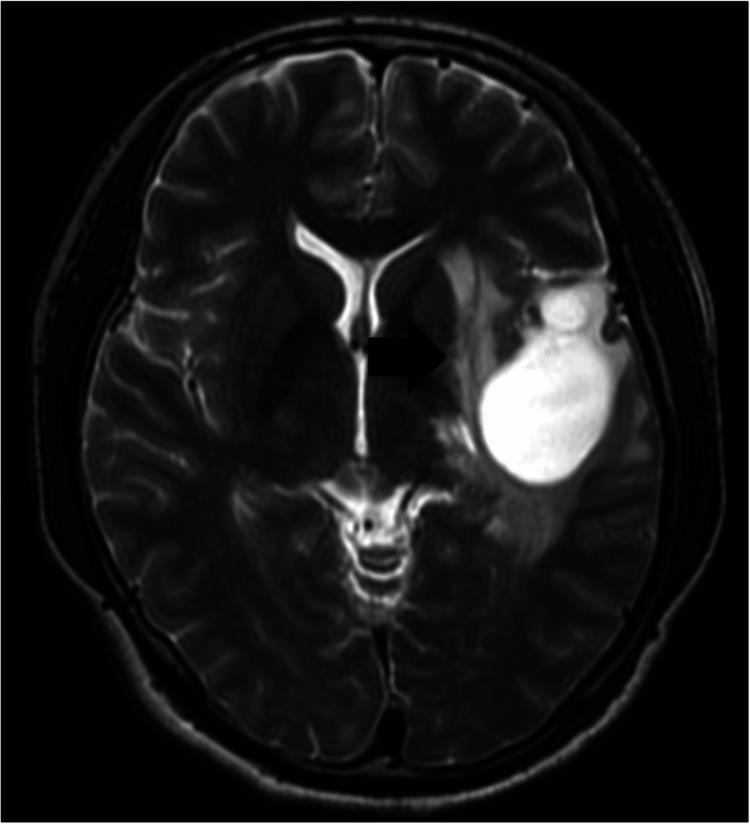

We report the case of a 29-year-old man who presented with a sudden headache. Computed tomography showed a small intraventricular hemorrhage in the left lateral ventricle. Cerebral angiograms suggested rupture of a coexisting feeder aneurysm in the left temporal cerebral arteriovenous malformation (AVM). The left proximal middle cerebral artery, a major feeding artery, was occluded near the AVM, with development of abnormal blood supply, such as in moyamoya-like vessels to the nidus. After endovascular embolization of the coexisting feeder aneurysm and feeding arteries, the patient underwent volume-staged Gamma Knife radiosurgery (GKS). Follow-up angiograms performed 4.5 years after the last GKS confirmed complete disappearance of the AVM. Around 4.8 years after GKS, the patient required surgical intervention to develop delayed cyst formation; however, the postoperative course was uneventful.